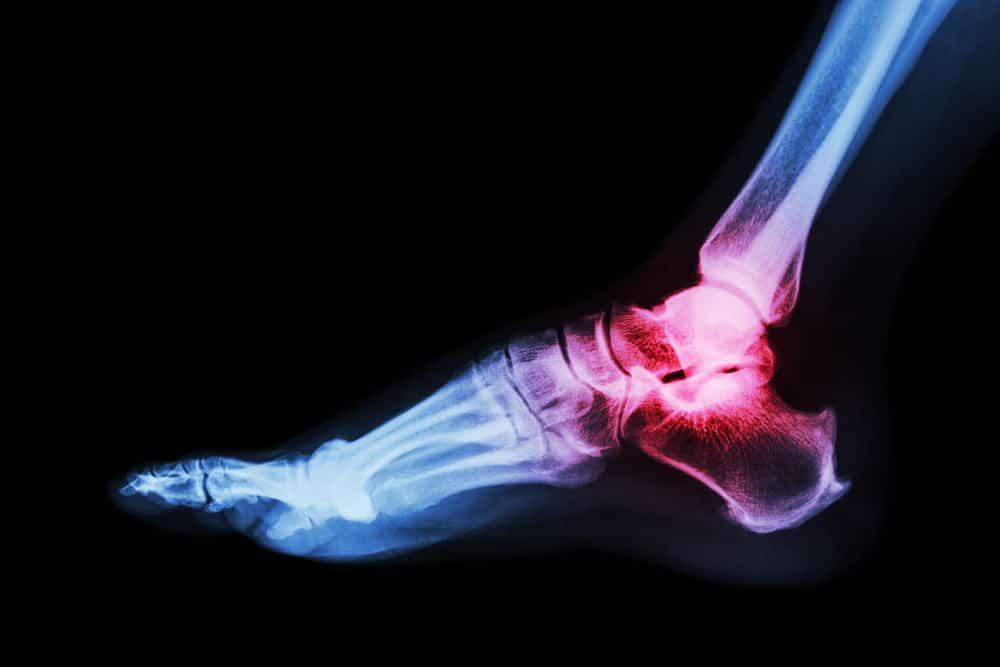

Gejala asam urat dan pseudogout yang mirip yaitu keduanya sama-sama menimbulkan rasa nyeri luar biasa di salah satu persendian Anda. Nyeri sendi mungkin diikuti dengan pembengkakan dan warna kulit jadi kemerahan. Serangan tersebut biasanya terjadi secara tiba-tiba.

Perbedaan gejalanya terletak pada sendi yang diserang. Asam urat biasanya menyerang jempol kaki, tumit, ujung jari, dan pergelangan tangan atau kaki. Sedangkan pseudogout sering menyerang sendi yang lebih besar misalnya lutut, bahu, siku, pinggul, dan punggung.